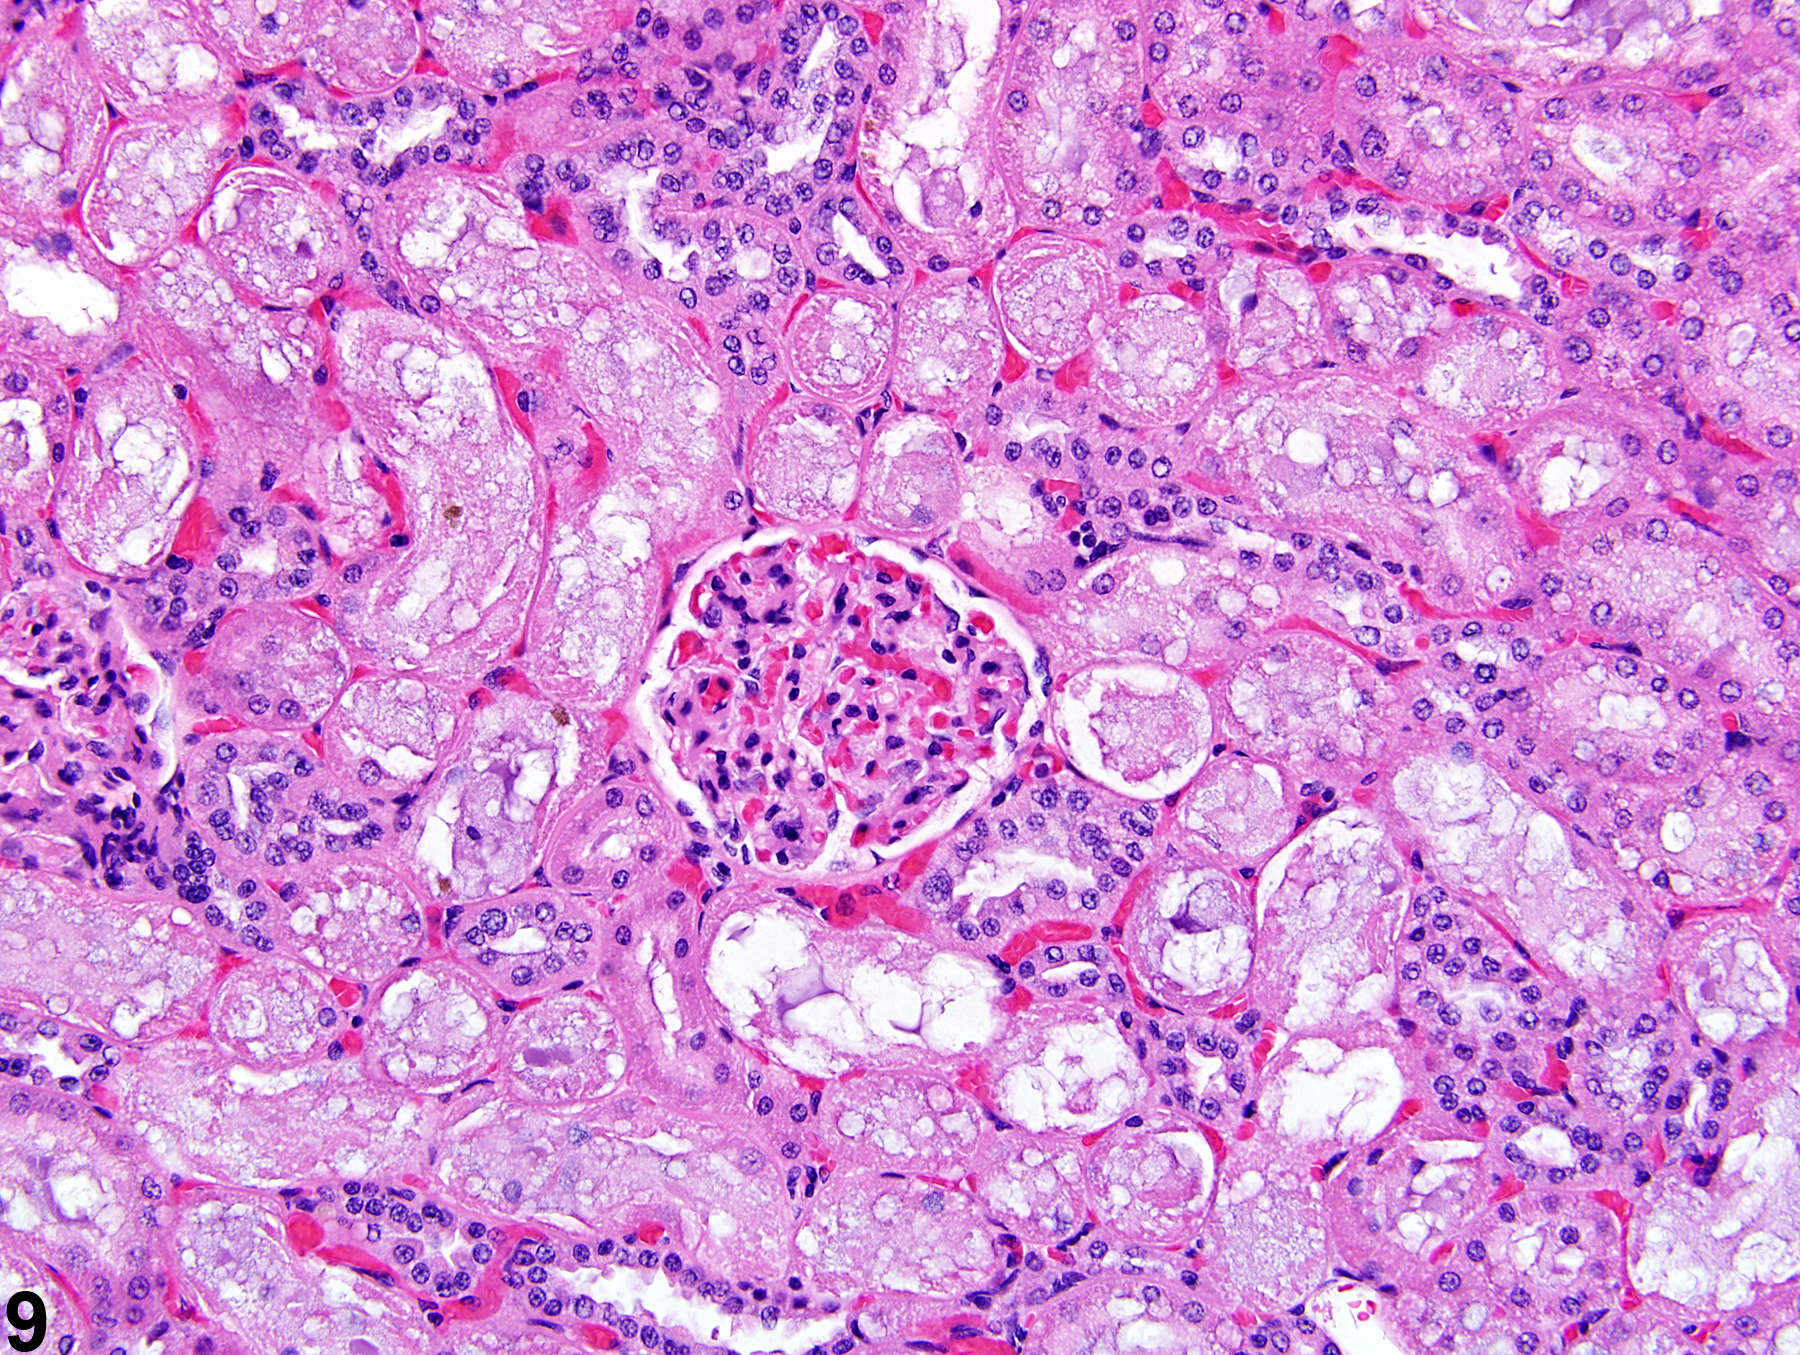

Карнификация Легкого: Микропрепараты и Диагностика

Раздел: Калейдоскоп образов